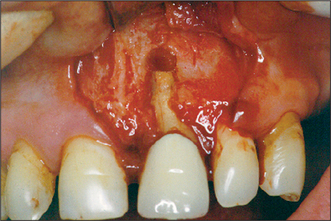

The potentially adverse influence of coexisting periodontal disease such as horizontal or vertical bone loss on the prognosis of surgical endodontics (Fig. 6.3)

Fig. 6.3 A flap has been raised here, exposing a lack of labial bone, which reduces the chances of success for surgical endodontics.